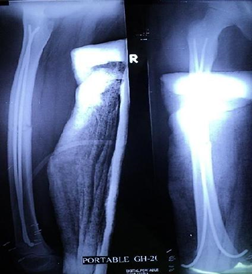

Figure 5 Closed fracture shaft of right femur of a young child.

Figure 6 Post-operative x ray.